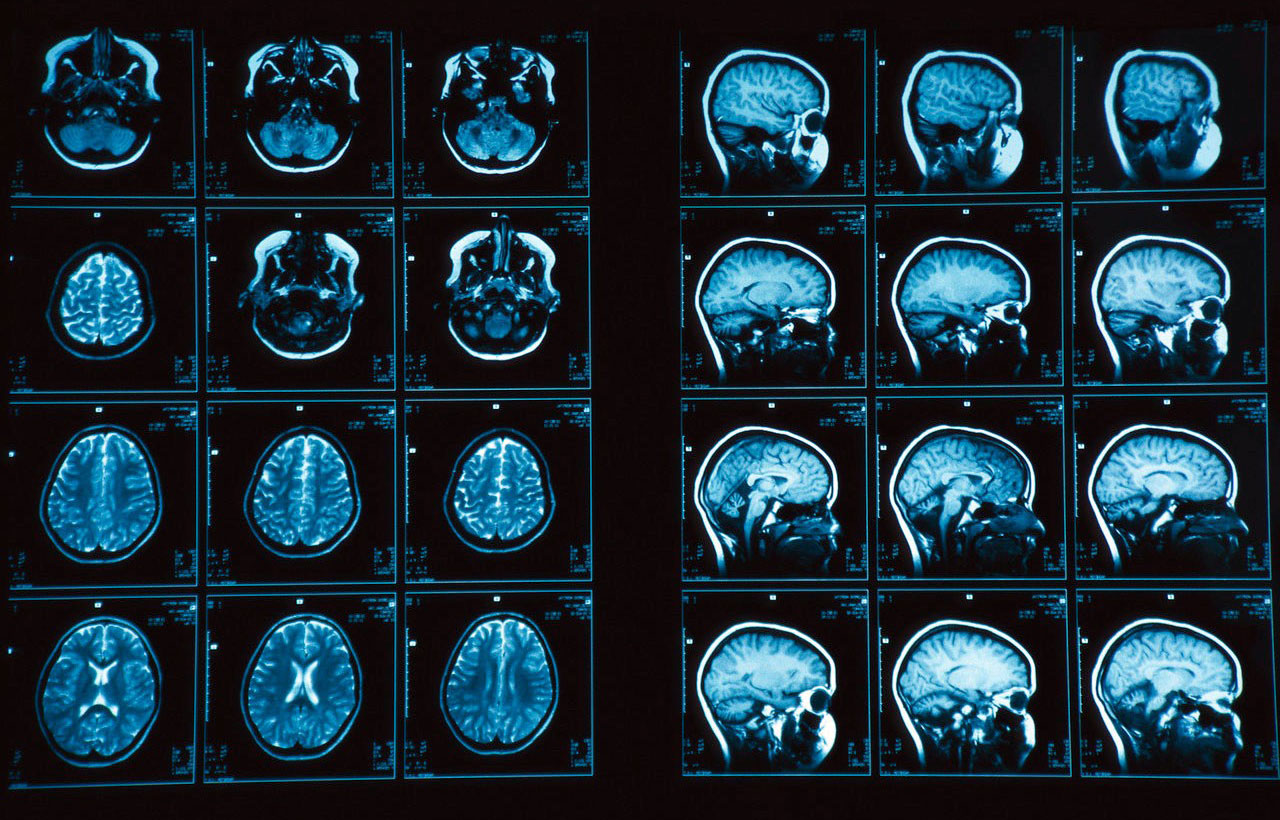

В эпоху стремительного развития технологий искусственного интеллекта (ИИ), его применение в медицине открывает новые горизонты для диагностики и лечения заболеваний. Мы, команда энтузиастов и профессионалов в области машинного обучения и нейронаук, решили внести свой вклад в эту революцию. Нашей целью стало создание ИИ, способного анализировать изображения магнитно-резонансной томографии (МРТ) головного мозга, чтобы помочь врачам в оценке степени поражения и принятии более точных решений о лечении.

Первым шагом на пути к созданию ИИ для анализа МРТ снимков стало четкое определение задачи. Мы решили сосредоточиться на оценке степени поражения мозга при различных заболеваниях, таких как инсульт, рассеянный склероз и опухоли. Это позволило нам сфокусировать наши усилия и разработать алгоритмы, оптимизированные для конкретных типов патологий.

Мы использовали глубокую сверточную нейронную сеть, состоящую из нескольких слоев свертки, пулинга и полносвязных слоев. Архитектура сети была разработана таким образом, чтобы эффективно извлекать признаки из МРТ снимков и классифицировать их в соответствии со степенью поражения мозга. Мы также использовали методы аугментации данных, такие как поворот, масштабирование и сдвиг изображений, чтобы увеличить размер обучающей выборки и повысить устойчивость модели к различным артефактам и вариациям в данных.

Перед подачей МРТ изображений в нейронную сеть, мы провели ряд этапов предварительной обработки. Это необходимо для улучшения качества изображений и повышения точности анализа. Этапы предварительной обработки включали: